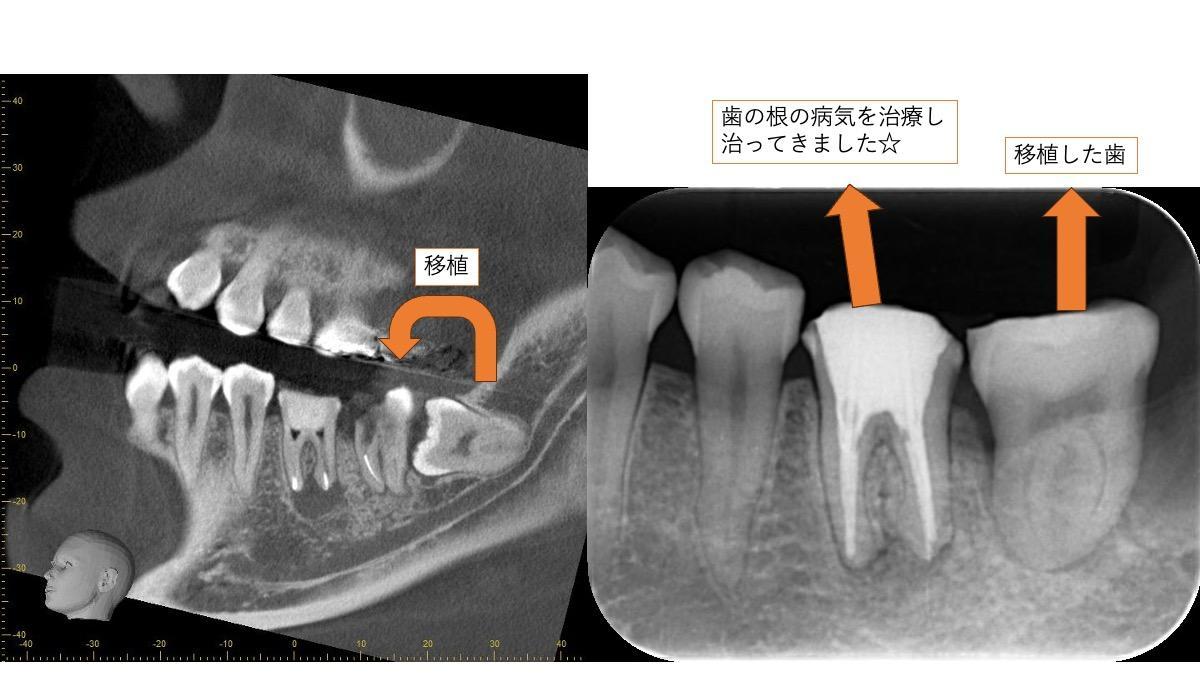

こちらの症例は、親知らずを手前の歯に移植したケースです。

余談ですが、手前の歯は根の病気があり、それの治療もうまくいきました。